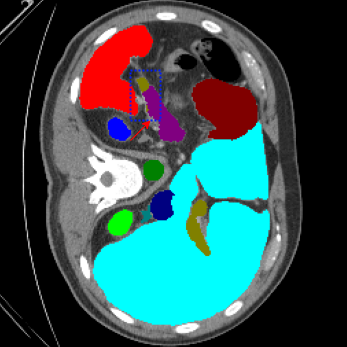

We begin by qualitatively inspecting our model. Figure 3 compares the output of LoGoNet to the best performing baseline model in BTCV dataset, i.e., DiNTS Search (more qualitative comparisons can be found in appendix section 11). We see that our model particularly excels in segmenting organ boundaries. This can be attributed to our effective strategy for extracting local-range dependencies, which plays a crucial role in extracting details from input data. Our model’s adeptness in capturing long-range dependencies allows it to grasp contextual information that extends over significant distances within the data. Simultaneously, its proficiency in handling short-range dependencies ensures precision in capturing localized patterns.